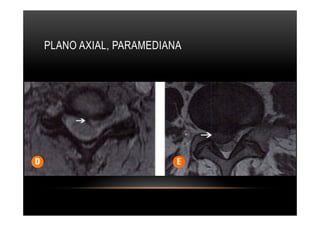

PLANO AXIAL, PARAMEDIANA

DISCO •  Classificação quantolocalização planos •  Plano Axial (transversal) •  Central (mediana posterior) •  Paramediana Direita/esquerda •  Recesso lateral Direita/esquerda •  Foraminal Direita/esquerda (forame neural) •  Extraforaminal (fora do forame neural, também conhecida como lateral extrema). •  Zona anterior (regioes anterior e antcrolatcral). •  Plano Sagital (Vertical) •  Suprapedicular •  Na altura do pedículo. •  Infrapedicular